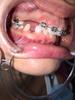

3.... фото не для слабонервных

В общем ВЧ месяц и в субботу поставили мне на НЧ, вчера так все болело, что не было сил писать.

Меня отфоткали и прикладываю еще фотки для сравнения, где БС неделька.

Еще у меня крутой аксесс в виде съемной пластины с зубами) дикция в ней ужасная, мне она максимально сильно не нравится.

зубы дракона да минимум три импланта пока планируется..

aav с костной тканью конечно же все не так хорошо, но будут пересаживать. Это вопрос, который будет обсуждаться через годик, а пока надо на место поставить то, что есть.